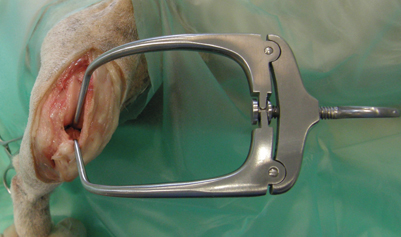

Stifle Distractory Wallace, Crossover, 100mm

- Designed to improve visualisation of the stifle joint

- One tip is inserted into the intercondylar notch and the other under the intermeniscal ligament

Self-retaining distractor allows the surgeon to have both hands free

Crossover Tips